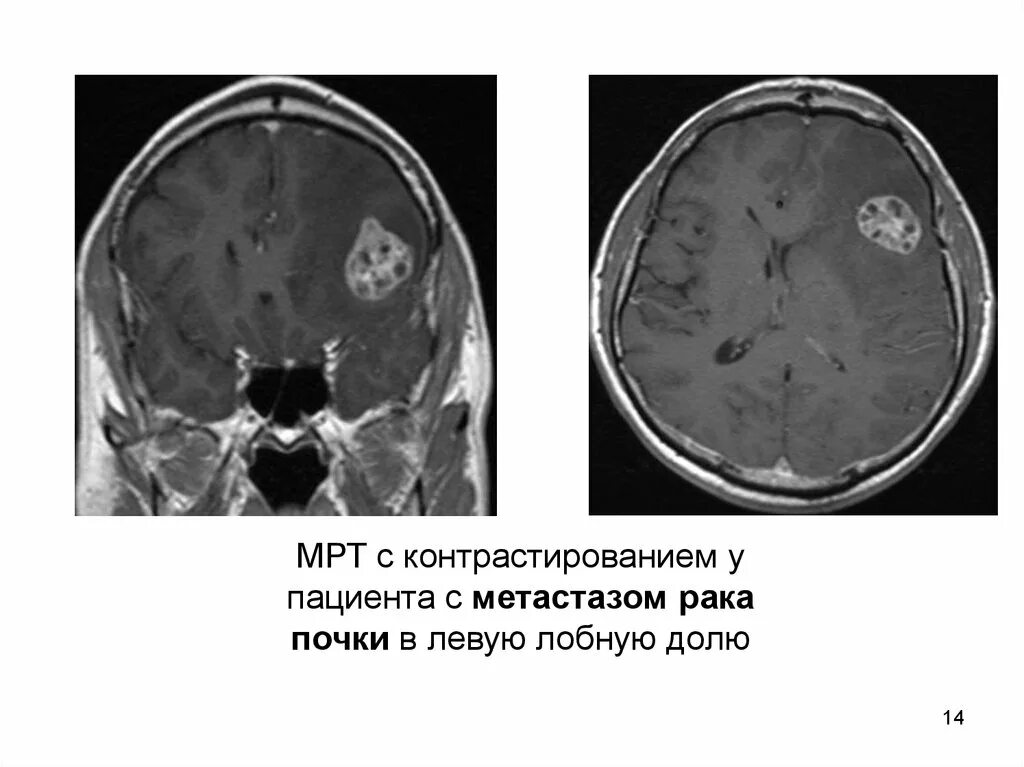

Метастазы рака почки